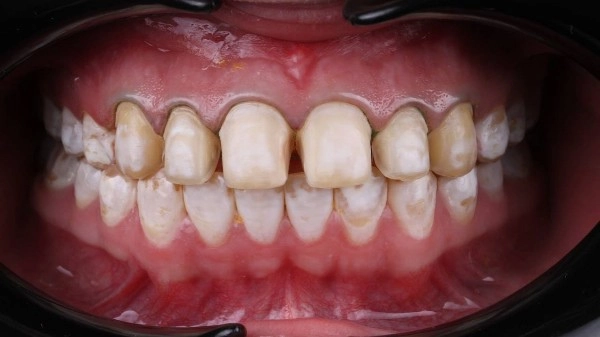

Как проявляется флюороз: ⠀⠀

Зубная эмаль утрачивает блеск.⠀

Появляются пятна и полоски, как правило, на передних резцах верхней челюсти. В зависимости от стадии течения болезни цвет колеблется от беловато-серого до коричневого.⠀

Зубы начинают болезненно реагировать на холодную и горячую пищу и жидкость.⠀

Зубы в местах пигментации становятся хрупкими, склонными к сколам и разрушению.⠀

Как вылечить флюороз: ⠀

На начальном этапе проводится отбеливание, а затем назначается курс реминерализации. Возможно назначение медикаментов.⠀

При поражениях средней и тяжелой степени восстановить эмаль естественным образом уже невозможно. Вернуть зубам эстетичный вид можно при помощи композитных материалов, керамических виниров или коронок.⠀

На фото работа врача стоматолога - ортопеда Сергеевой Анастасии Сергеевной.